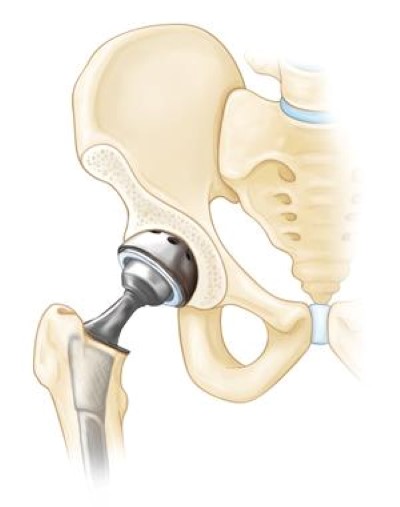

Total hip replacementYour doctor will remove both the damaged acetabulum and femoral head, and then position new metal, plastic, or ceramic joint surfaces to restore the function of your hip.

Hip replacement implants

In total hip replacement, both the head of the femur and the socket are replaced with an artificial device.